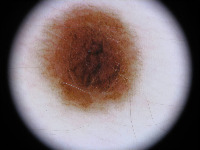

Dermatology Research: Researchers studying skin conditions could use this model to detect changes in the skin color, texture, or other characteristics over time. The model could help identify early signs of skin diseases and track their progression or regression.